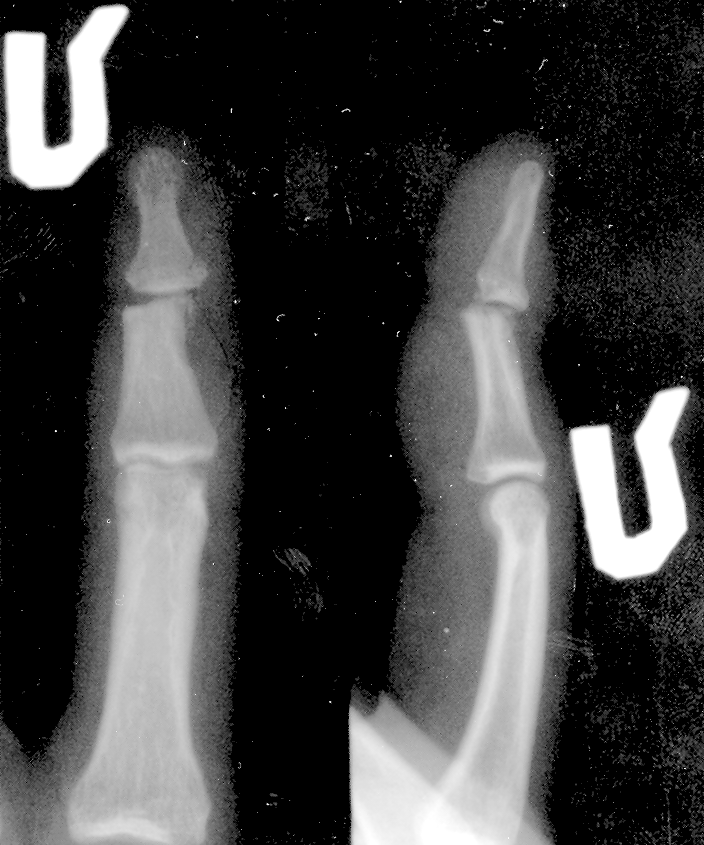

Подскажите варианты личения,как вернуть подвижность?сухожилие сгибателя не повреждено,а сухожилие разгибателя(нет фрагмента)снимок и выписка прилагается.Зарание спасибо!!!